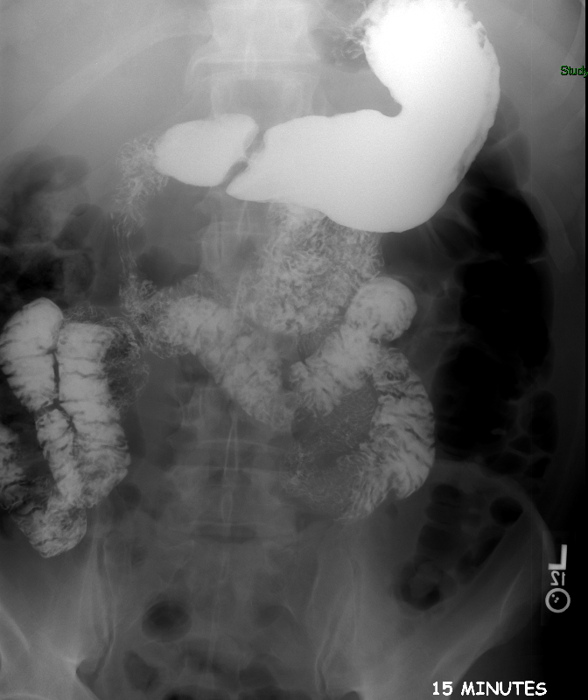

- Once 15 minutes has passed since the patient drank the barium, the technologist will obtain a prone (if possible) radiograph

(key image 2).

- Prone positioning is preferred because while lying prone, the weight of the body provides compression of the bowel loops.

- The film should include the entire stomach as well as the bowel that is filled with contrast.